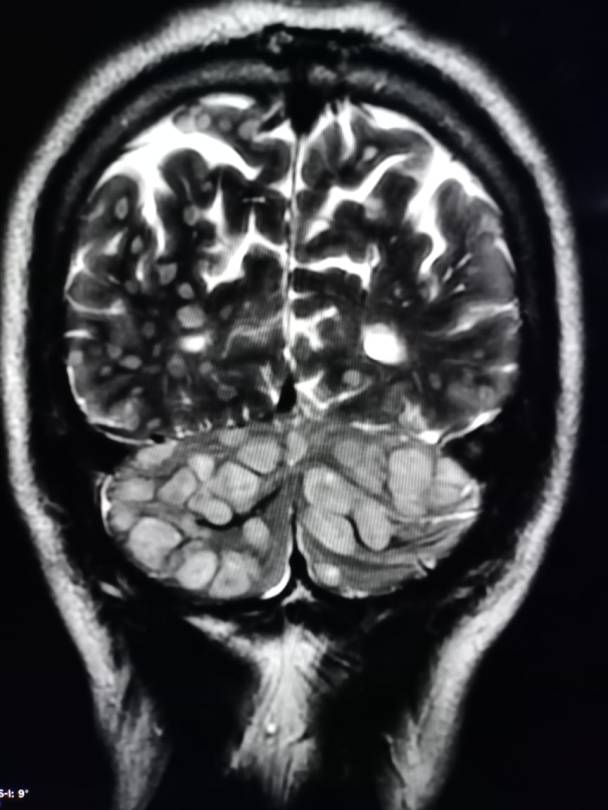

neurocystiscircosis-

864 × 1152